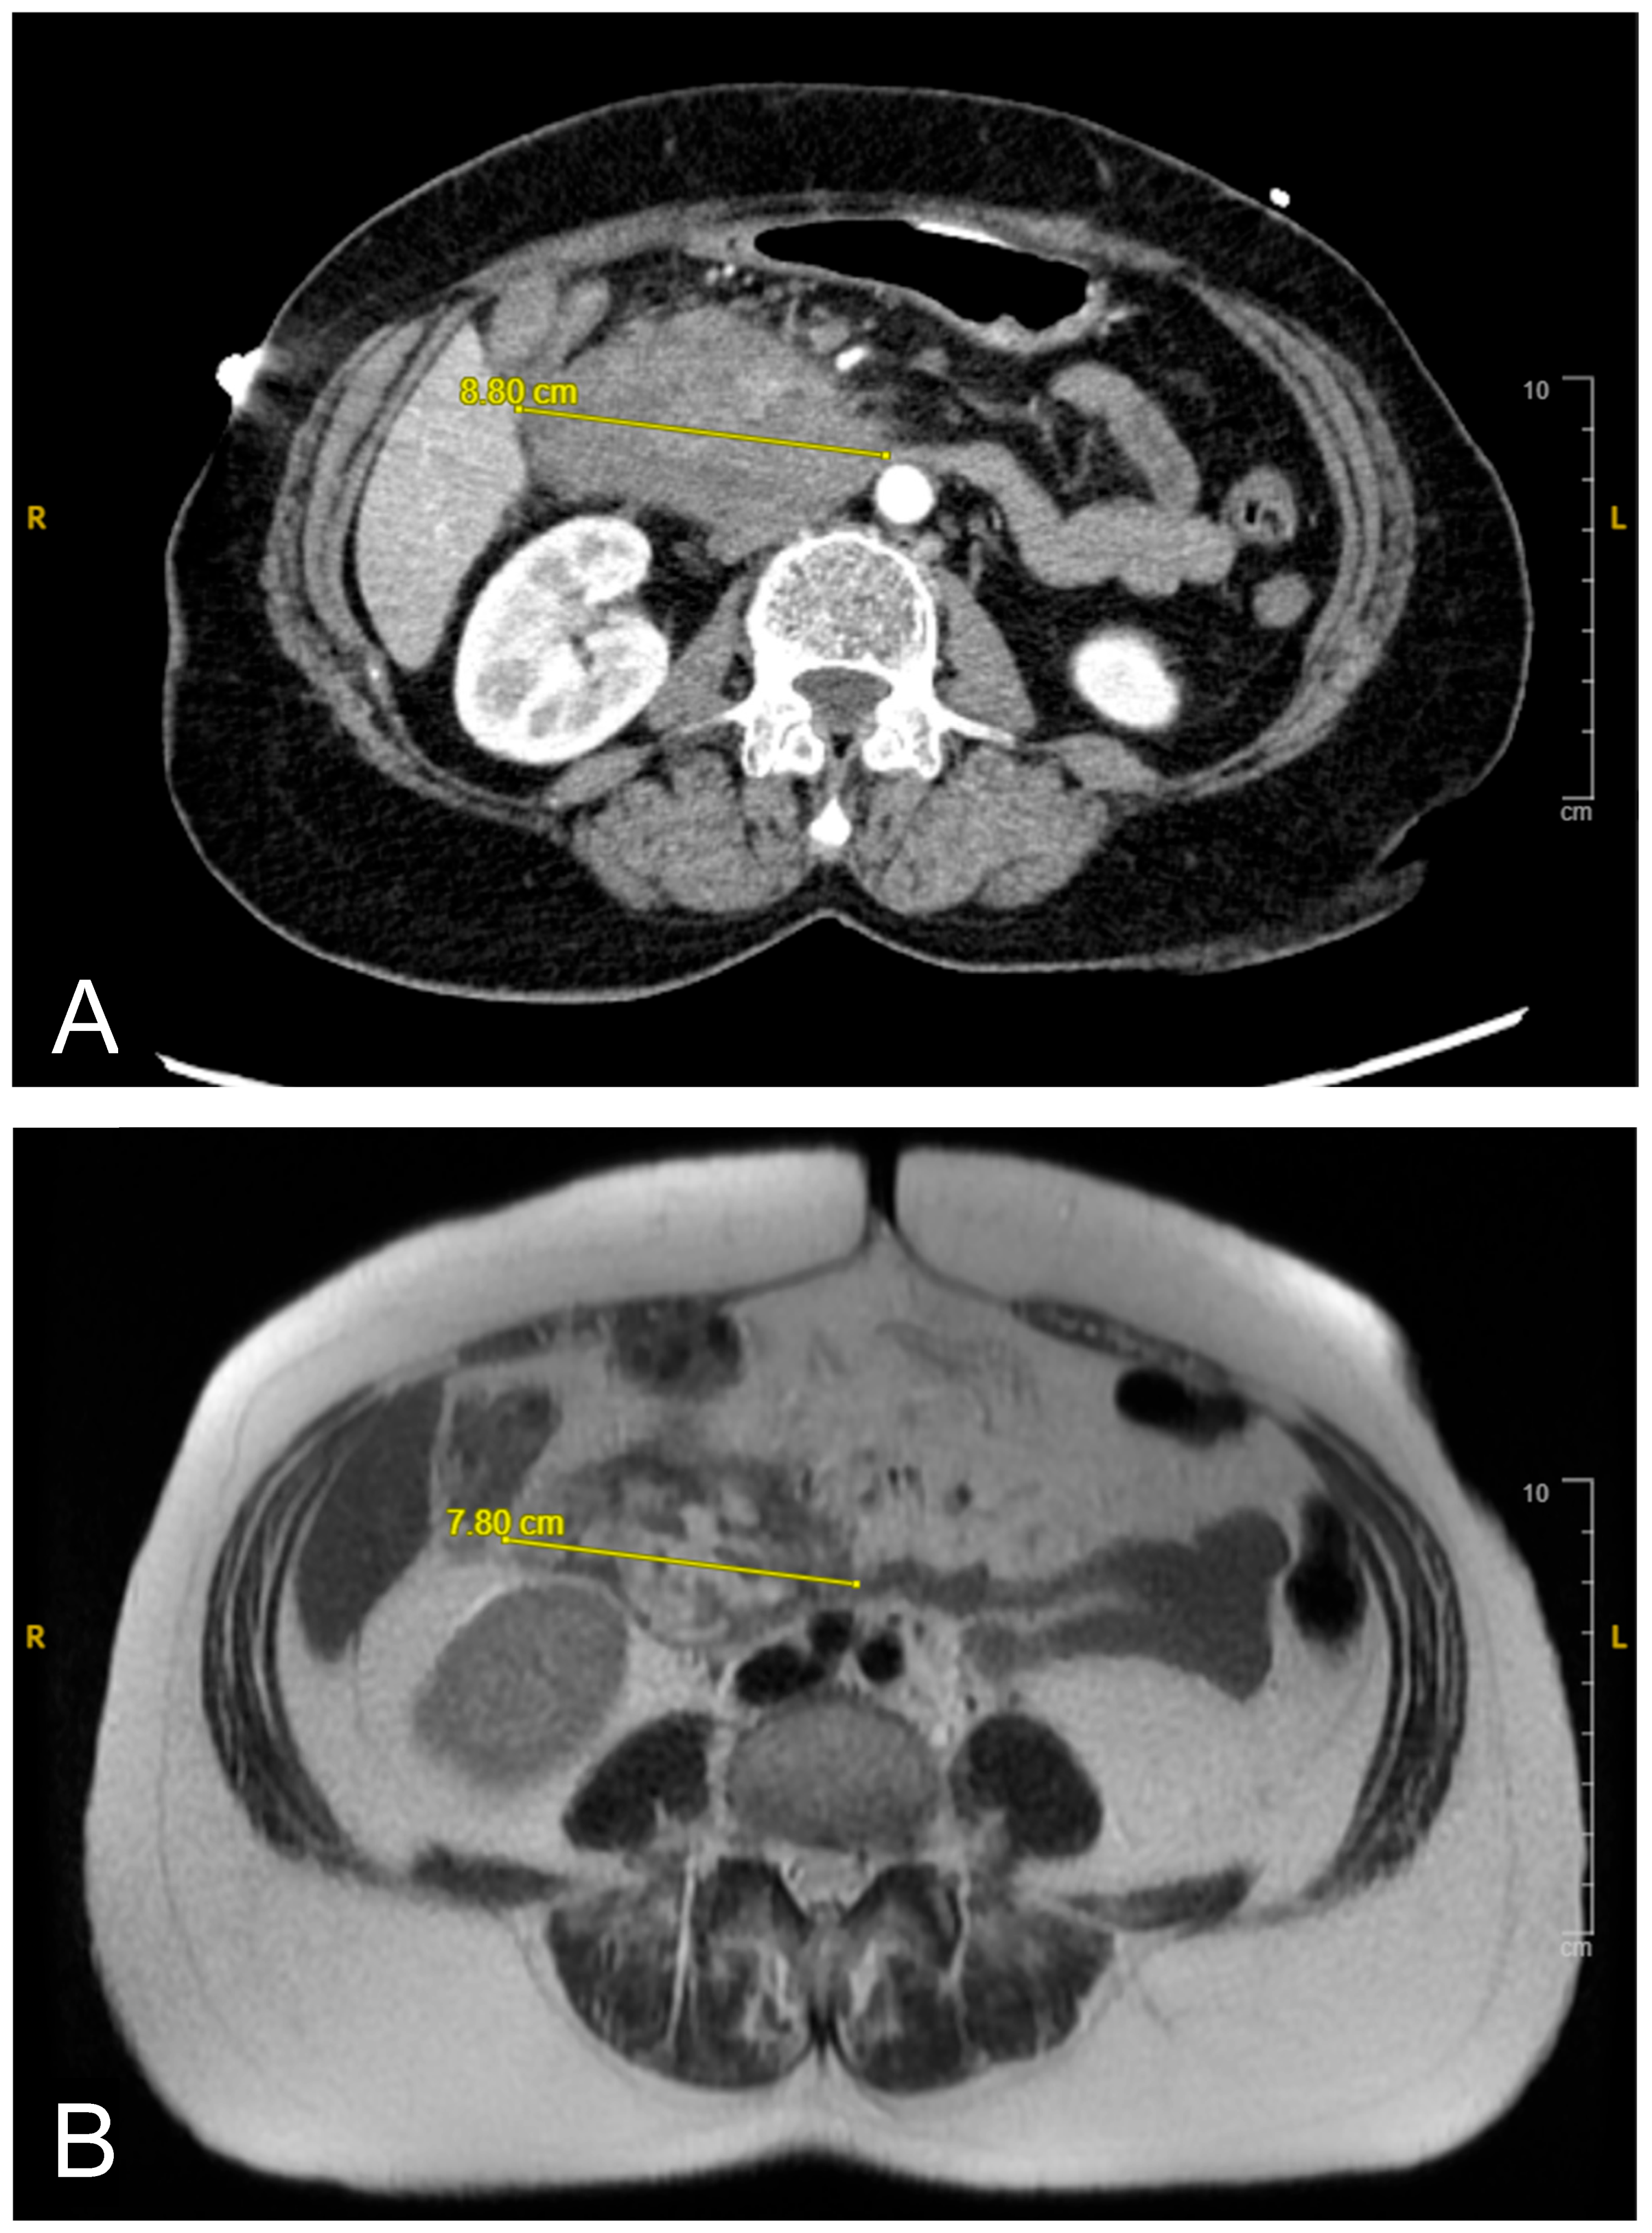

A CT scan of the abdomen revealed a heterogeneous lesion measuring 6.1 cm × 8.8 cm × 8.7 cm in the second portion of the duodenum with mild heterogeneous enhancement (Figure 1A). Given the imaging features, a duodenal malignancy was initially suspected. The attending physician decided to pursue further investigations to rule out malignancy, and the patient was admitted for a comprehensive evaluation to establish a definitive diagnosis. The following day, an MRI cholangiogram with contrast was performed, revealing a lesion measuring 7.8 cm × 5.8 cm, in the second and third parts of the duodenum. The lesion exhibited heterogeneity with a lack of enhancement, indicative of a duodenal hematoma (Figure 1B). The hematoma affected the duodenum and the head of the pancreas, likely causing extrinsic compression with mild bile duct dilation.

Over the following days, the NG tube suction output remained significant (1–1.5 L daily), and the liver function tests (LFTs) showed a slow uptrend with mixed hepatocellular and cholestatic pattern, likely due to extrinsic compression on the distal common bile duct from the duodenal hematoma. NJ feeding continued, with close monitoring of NG suction output. The patient tolerated the NJ feeds well, and the LFT showed slight improvement. A repeated MRI revealed a reduction in the hematoma size (from 7.8 cm × 5.8 cm to 6.2 cm × 2.5 cm as shown in Figure 3), along with decreased duodenal wall thickness and hyperenhancement. A follow-up EGD revealed improved non-bleeding gastric ulcer and successful passage of the scope through the second portion of the stenosed duodenum.

Figure 1. (A): Initial contrast-enhanced abdominal CT scan revealing duodenal hematoma measuring 8.8 cm in its widest diameter. (B): Follow-up MRI cholangiogram showing interval regression in size to 7.8 cm. Image quality was limited by motion artifact.